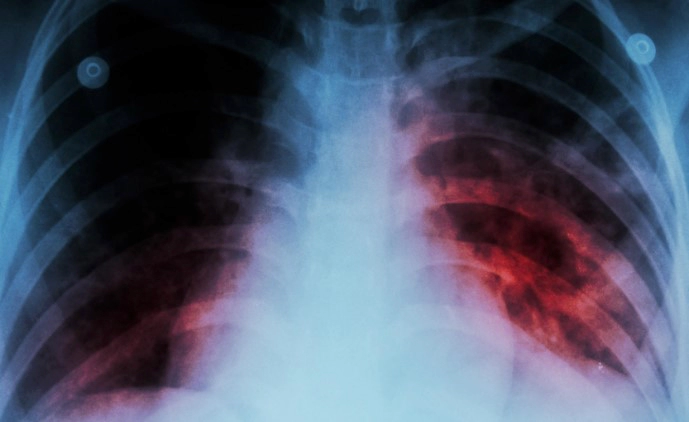

결핵은 여전히 전 세계적으로 중요한 감염 질환으로 남아 있으며, 특히 잠복결핵은 감염자가 아무런 증상을 느끼지 않기 때문에 진단이 어렵고, 이로 인해 더욱 위험한 상태가 될 수 있습니다. 이에 잠복결핵의 증상을 파악하는 방법, 보건소와 병원에서 사용되는 검사 방법, 그리고 이러한 검사에 따른 비용에 대해 최대한 정리해 보았습니다.

잠복결핵은 결핵균에 감염되어 있지만 증상이 나타나지 않는 상태를 말합니다. 이런 사람들은 일반적으로 감염의 초기 단계에서 결핵 질환을 전파하지 않으며, 결핵이 활성화되기 전까지 아무 증상없는 상태를 유지합니다.

이는 마치 결핵균이 "잠자고 있는" 상태와 비슷하다고 볼 수 있으며, 이 때문에 이를 '잠복 결핵'이라고 부릅니다. 약 10%의 잠복 결핵 환자들이 평생 중 어느 시점에서든 결핵으로 질환을 발병하게 됩니다. 그리고 이 비율은 면역 체계가 약화된 사람들, 예를 들면 HIV 감염자나 특정 약물을 복용하는 사람들에서는 훨씬 높아집니다.

잠복 결핵은 그 이름에서 알 수 있듯이 증상이 보이지 않는 상태를 말합니다. 결핵균에 감염되어 있지만, 몸의 면역 체계가 균을 잠재워서 병이 발병하지 않는 상태입니다. 이 때문에 잠복 결핵은 보통 증상을 보이지 않습니다. 다만 이 상태에서 몸의 면역 체계가 약해지면, 균이 다시 활성화되어 결핵 병을 발병시킬 수 있습니다. 이럴 경우에는 명확한 증상이 나타날 수 있습니다. 이러한 증상들은 결핵 병의 증상이며, 잠복 결핵이 활성화된 상태를 반영합니다.